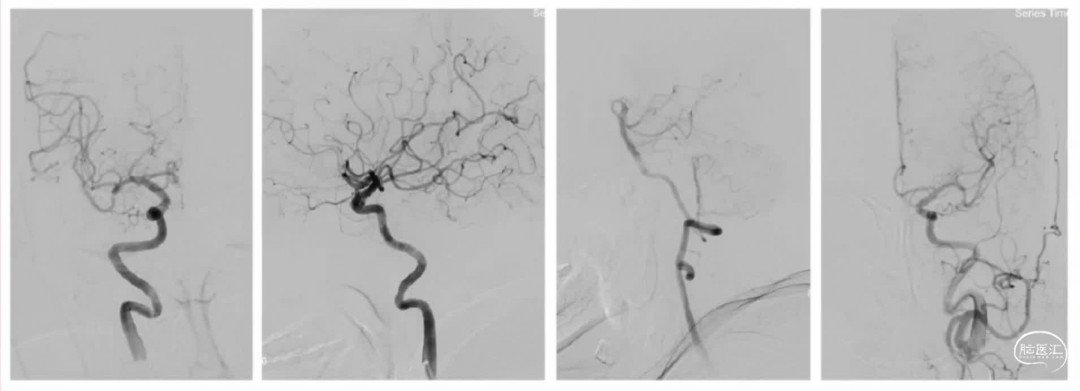

病史简介 4

主诉: 71岁,男性,突发左侧肢体活动不灵伴言语不清4.5小时(院外溶栓后转入)

查体:神志模糊,双侧瞳孔等大等圆,直径2.5mm,对光反射存在,双眼右侧凝视,右侧上肢肌力0级,下肢2级。NIHSS:17分。

既往史: 高血压病史10年。

2、远端血管闭塞多是检塞事件,栓子随时可能发生动态变化,术前NIHSS评分高,可能是大血管闭塞且侧枝代偿差,已经形成较大的核心梗死,因栓子远端移位术中表现为远端血管闭塞,此时尽管开通满意,但术后过度灌注损伤、脑出血风险比较高,临床预后并不满意,此时应适可而止。